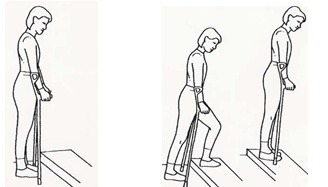

نکاتی در مورد بالا و پایین رفتن از پلهها: پلکان بدون نرده

به کمک چوبهای زیر بغلی که نزدیک به پلهها نگه داشتهاید بایستید و از پلهها بالا بروید. اول پای سالم را روی پله بالایی بگذارید، سپس پای عمل شده را بلند کنید. در انتها چوبهای زیر بغل را روی پلهها بگذارید.

برای پایین آمدن از پلهها ابتدا چوبهای زیر بغل را روی پله پایینتر بگذارید، سپس پای عمل شده و در نهایت پای سالم را روی همان پله پایینی بگذارید.

برای پایین آمدن از پلهها ابتدا چوبهای زیر بغل را روی پله پایینتر بگذارید، سپس پای عمل شده و در نهایت پای سالم را روی همان پله پایینی بگذارید.